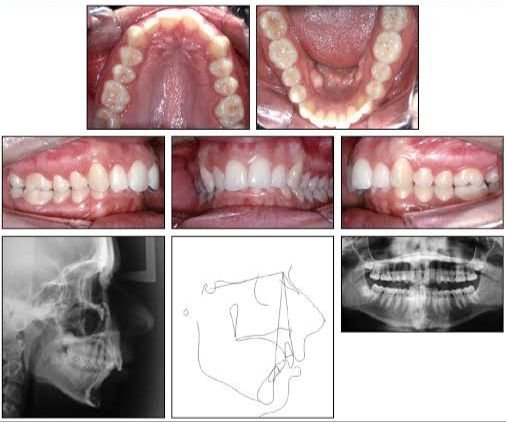

MOST POPULAR TREATMENTS

What we offer